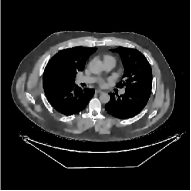

This section compares the reconstruction quality and runtime among the proposed MBIR method, PWLS-ST-, and other three MBIR methods, PWLS-EP, PWLS-DL, and PWLS-ST-. Table I shows that, for both 2D and 3D sparse-view CT reconstructions of the XCAT phantom, the proposed PWLS-ST- model outperforms PWLS-EP and PWLS-ST- in terms of RMSE. In addition, PWLS-ST- using a square transform (of size ) achieves lower RMSE than PWLS-DL using an overcomplete dictionary (of size ) for 2D sparse-view reconstructions. Fig. 3(a) and Fig. 4 show the reconstructed images for 2D and 3D phantom experiments, with different reconstruction models and different number of views. (See the corresponding error maps in the supplement.) The proposed PWLS-ST- consistently gives more accurate image reconstructions compared to other MBIR methods. Specifically, PWLS-ST- has smaller errors in the heart region (see zoom-ins in Fig. 3(a)) of 2D reconstructions than PWLS-DL and PWLS-ST-. In addition, compared to PWLS-ST-, PWLS-DL and PWLS-ST- have some ringing artifacts around the edges with high transition, e.g., edges between air and soft tissues. (See a comparison of profiles of PWLS-ST- and PWLS-ST- in the supplement.) In particular, PWLS-ST- and PWLS-DL give more visible ringing artifacts for 2D reconstruction from fewer views, and PWLS-ST- has these ringing artifacts for 3D reconstructions regardless of the number of views (see zoom-ins in Fig. 4). Table II reports runtimes of different MBIR methods in reconstructing the -views XCAT phantom scan. (FBPConvNet is a non-MBIR method and its runtime for processing a image is approximately one second with a TITAN Xp GPU.) While providing better reconstruction quality, the proposed Algorithm 1 of PWLS-ST- has shorter runtime compared to the algorithms of PWLS-DL and PWLS-ST- in Section III-A. Similar to the PWLS-EP algorithm, the reconstruction time of the PWLS-DL, PWLS-ST-, and PWLS-ST- algorithms can be further reduced by using ordered subsets [51].

Fig. 3(b) shows that when tested on the clinical scan data, the proposed PWLS-ST- method improves reconstruction quality in terms of noise and artifacts removal (e.g., see zoom-ins for soft-issue regions), and edge preservation (e.g., see zoom-ins for bone regions), compared to PWLS-EP and PWLS-ST-. Compared to PWLS-DL, PWLS-ST- achieves comparable image quality, but requires less computational complexity.

| (a) 2D fan-beam CT experiments |